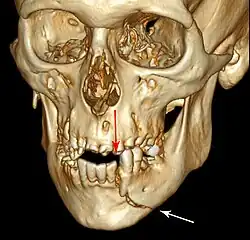

![]() | |

| 3D computed tomographic image of a mandible fracture in two places. One is a displaced right angle fracture and the other is a left parasymphyseal fracture. | |

Mandibular fracture, also known as fracture of the jaw, is a break through the mandibular bone. In about 60% of cases the break occurs in two places.[1] It may result in a decreased ability to fully open the mouth.[1] Often the teeth will not feel properly aligned or there may be bleeding of the gums.[1] Mandibular fractures occur most commonly among males in their 30s.[1]